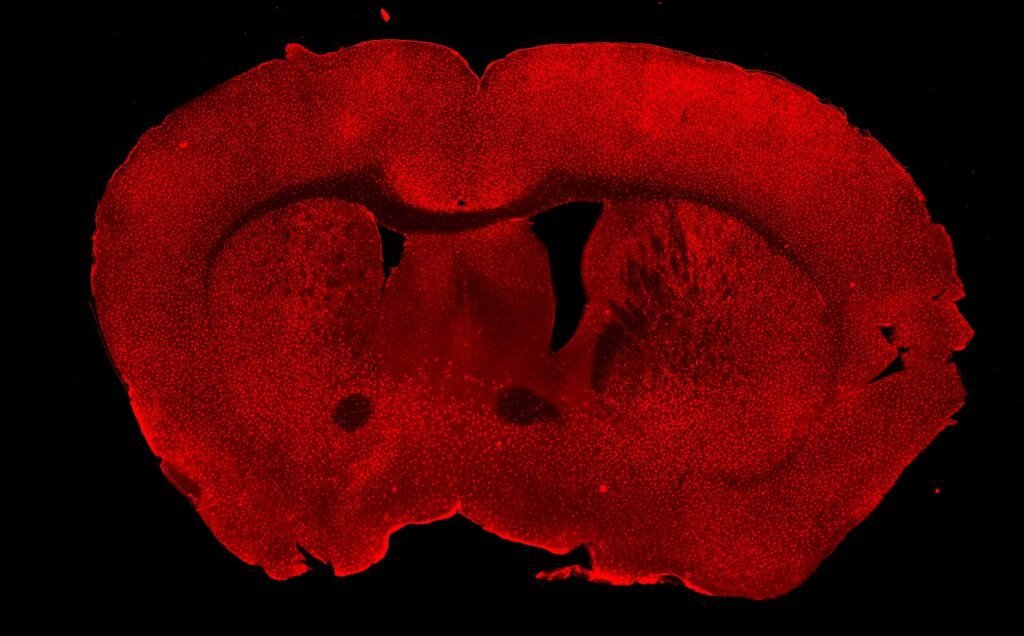

Information was available with The Chenab Times indicating that this research builds upon previous work that established microglia as both facilitators and inhibitors of anxiety in rodent models. Scientists at the University of Utah have now identified calcium as a crucial chemical signal that activates microglia during behaviours associated with anxiety and obsessive-compulsive disorder (OCD) in both healthy mice and those modelling chronic anxiety and OCD spectrum disorder (OCSD).

Naveen Nagarajan, assistant professor of paediatrics at the Pediatric Research Institute at the University of Louisville and the study’s first author, stated that microglia’s active control over these behaviours makes them a critical target for understanding and treating neuropsychiatric conditions. The research team employed genetic tools alongside light-based cell stimulation techniques to temporarily activate a specific group of microglia, termed ‘Hoxb8’, in healthy mice. This activation led to the mice exhibiting grooming and anxiety-like behaviours.

Observations showed a correlation between normal mice exhibiting grooming, freezing responses, or other anxiety-like behaviours and spikes in calcium levels within the Hoxb8 microglia. Conversely, when these behaviours ceased, calcium levels were observed to return to baseline. Furthermore, in mice genetically predisposed to chronic anxiety and OCSD, Hoxb8 mutant microglia consistently displayed high calcium levels.